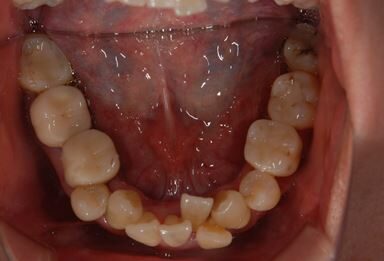

| 性別/年齢 | 女性 / 40歳 | ||||||||||||||||||||||||||||||||

| 主訴 | 前歯のつけ根の黒い部分を見えないようにしたい。 | ||||||||||||||||||||||||||||||||

| 治療方針 | 上顎前歯をセラミック治療にて審美的回復を行う。 | ||||||||||||||||||||||||||||||||

| 治療内容 | オールセラミッククラウン4本(セラミック用土台4本) | ||||||||||||||||||||||||||||||||

| 総治療費 | 573,300円 | ||||||||||||||||||||||||||||||||

| 治療期間 | 3ヶ月 |